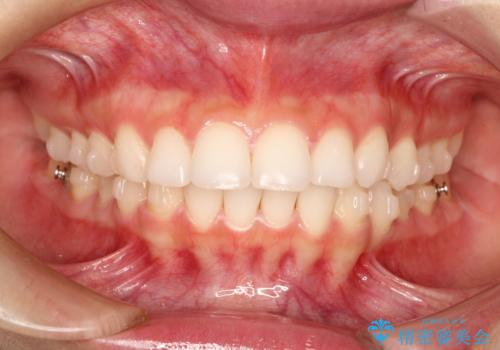

出っ歯の矯正治療 歯を抜かずにインビザラインで

- インビザラインで出っ歯を治したいとの希望がありました。

上顎の歯を全体的に後方に移動させて前歯を引っ込める計画としました。

インビザラインで目立たずに、痛みも少なく矯正治療を終えることができ満足していただけました。